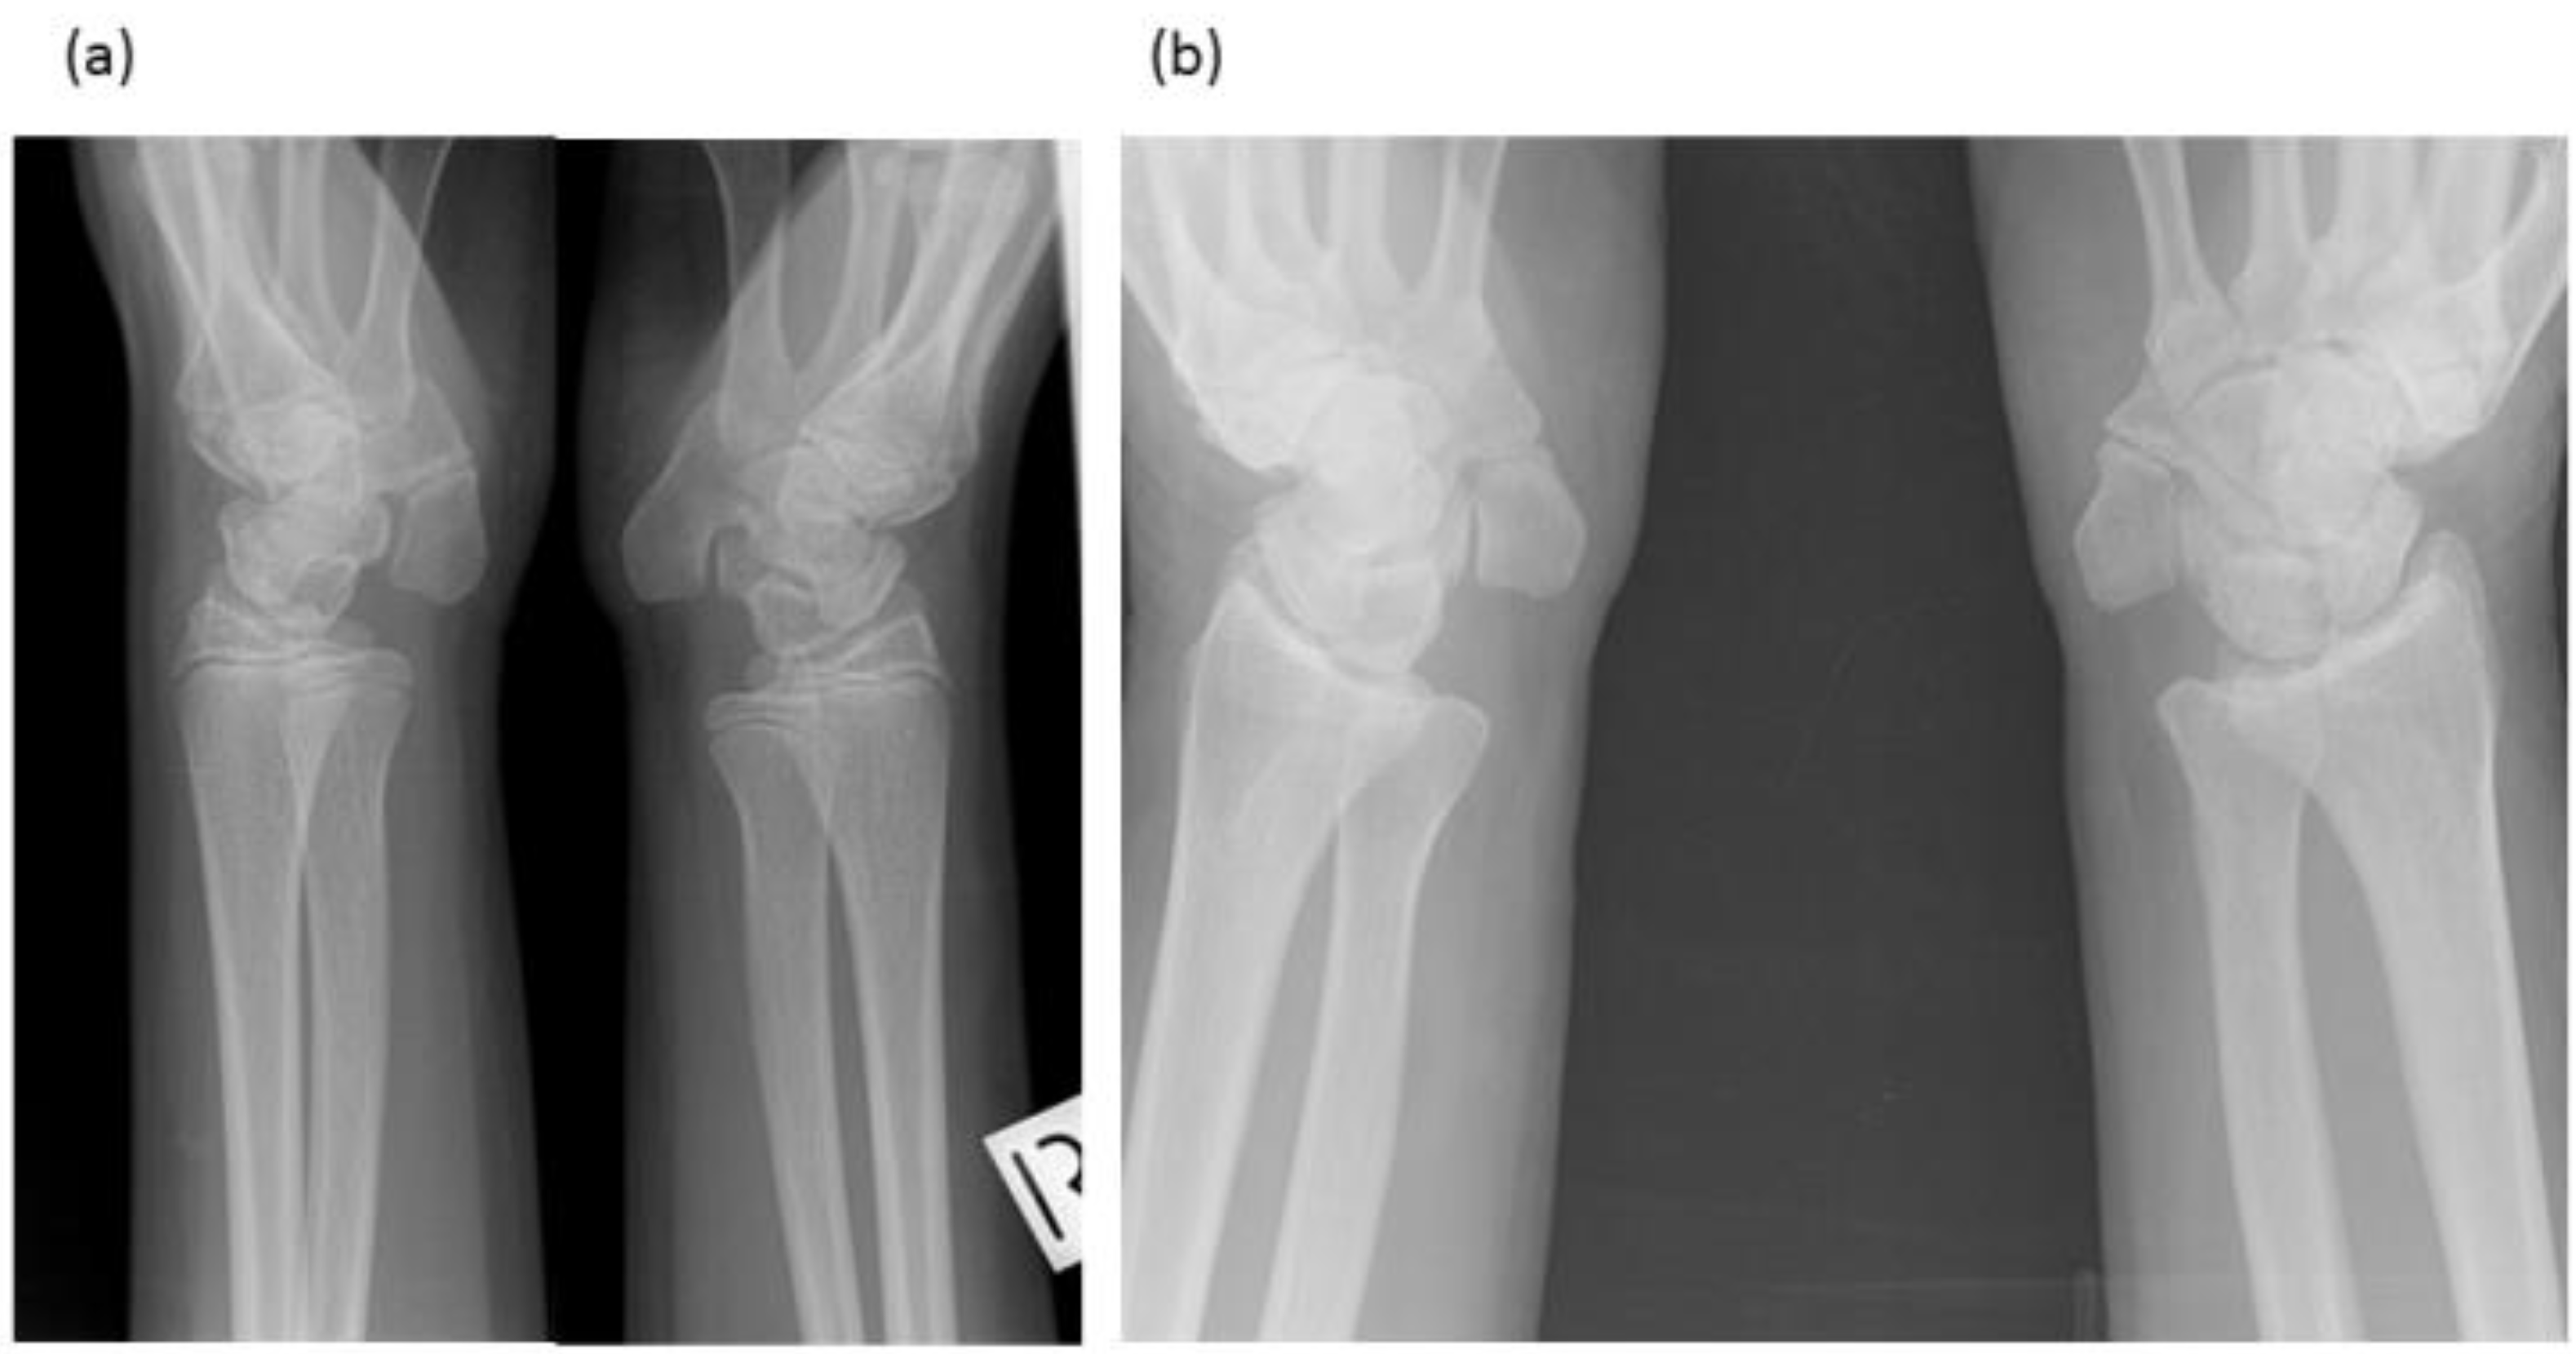

Figure 3.

Radiographs of wrists of: (a) Proband—display bilateral symmetry of elongation of the pisiforms. (b) Proband’s father—displays bilateral symmetry of elongation of the pisiforms which are different in length and morphology from those of the proband. Both father and daughter had restricted wrist rotation/supination and grasping and writing capacity.